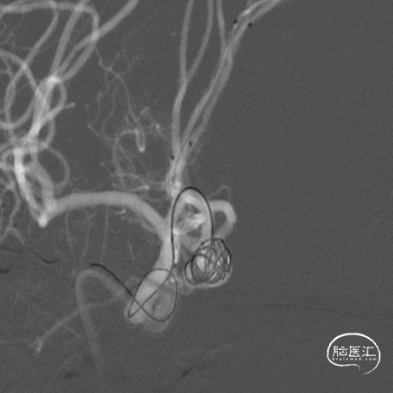

右侧Echelon-10瘤内成袢送入A2段,并解袢。

左侧Echelon-10瘤内成袢送入A2段,并解袢。

填入首枚10mm×30cm弹簧圈。

接续填入2枚9mm*30cm弹簧圈,再调整微管位置,送入4mm×12cm、4mm×10cm、3mm×8cm、2mm×6cm弹簧圈。

置入第一枚Atlas支架 3mm×15mm。

置入第二枚Atlas支架 4mm×21mm。